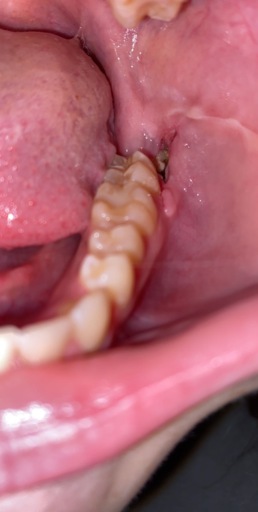

I have a very large cavity on one of my upper molars that caused severe pain for several weeks and went up through my sinuses. I live below the poverty level and have no insurance, but I headed to the ER because it was radiating out farther. I was put on penicillin and referred to our local, county health department where the only adult dental care offered is extraction. They have no anesthesia but did have Novocaine. He did an x-ray and said the roots were very deep but I know I don't have the option for a filling or root canal so I said that was fine. The Novocaine deadened every area of my mouth except the one nerve right in my tooth. I told him several times I was feeling pain, not pressure. After an hour of him attempting to extract the tooth, I had to have him stop because my whole body was shaking and I was sobbing no matter how much I tried to stop. I asked what now and there were no suggestions but he did inform me the tooth was still very firmly in my mouth and would not fall out on its own. For several days afterward, I had quite a bit of pain at the site of the injections (he injected in multiple locations 3 separate times)and the pain I had gone in with, though the radiating pain had stopped after completion of the penicillin. This was a month ago. I brush regularly and only use one side of my mouth to eat with because contact between the upper and lower teeth is very painful on the right side. This week, I have had some more aching but I figured I was just grinding my teeth again (yes, I have apnea and a bi-pap) but yesterday, the pain in the gum surrounding the tooth and roof of my mouth in the area where the dentist had done the injections returned as if he had been yanking on my tooth again. He did damage the tooth quite a bit during the attempted extraction with the ...pliers (not sure of the correct term) because I don't think he thought the tooth would be remaining. I am at a loss what to do now because I am already eating soft foods and the pain is bad enough, it woke me from sleep. I am taking an OTC NSAID, rinsing with salt water, and avoiding sugary or acidic foods. What else can I do?